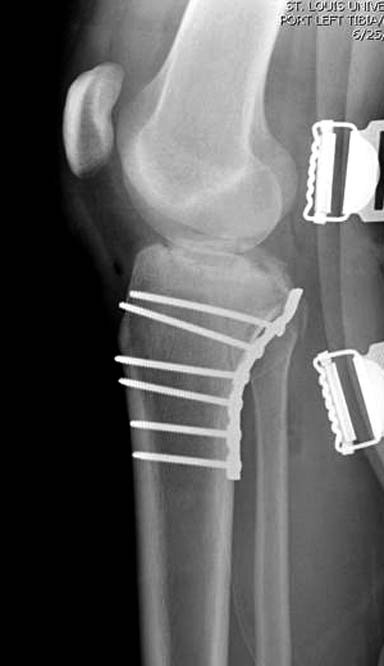

На боковом рентгене, явный задний смещенный компонент. КТ поможет увидеть "вершину" перелома, куда надо поставить антискользящую пластину из заднего или задне-медиальнего доступа. Для стабилизации боковой колонны традиционный боковой доступ через Girdle tubercle с длинной блокирующей пластиной. Одна задняя подпорка не удержит медиальную колонну, требуется длинная медиальная пластина.

Пластин для медиальной колонны не бывает, и поэтому подойдет любая тонкая пластина. Сегодня отходим от установки для тибиал плато толстых пластин, больше, чем 3.5 мм. Задача удержать, а нагрузка разрешается только после сращения в 3 мес., и поэтому нет смысла устанавливать толстые пластины

Перелом сложный, и для окончательного успеха потребуется арсенал фиксаторов и наличие опыта разных доступов. К успеху приведет только тщательное планирование. Возможно, фиксировать не удастся все за раз. Если во время операции возникнет опасность развития отека в ране, “damage control” операцию надо отложить, лучше поэтапно, чем осложнение.

.Здесь примеры...